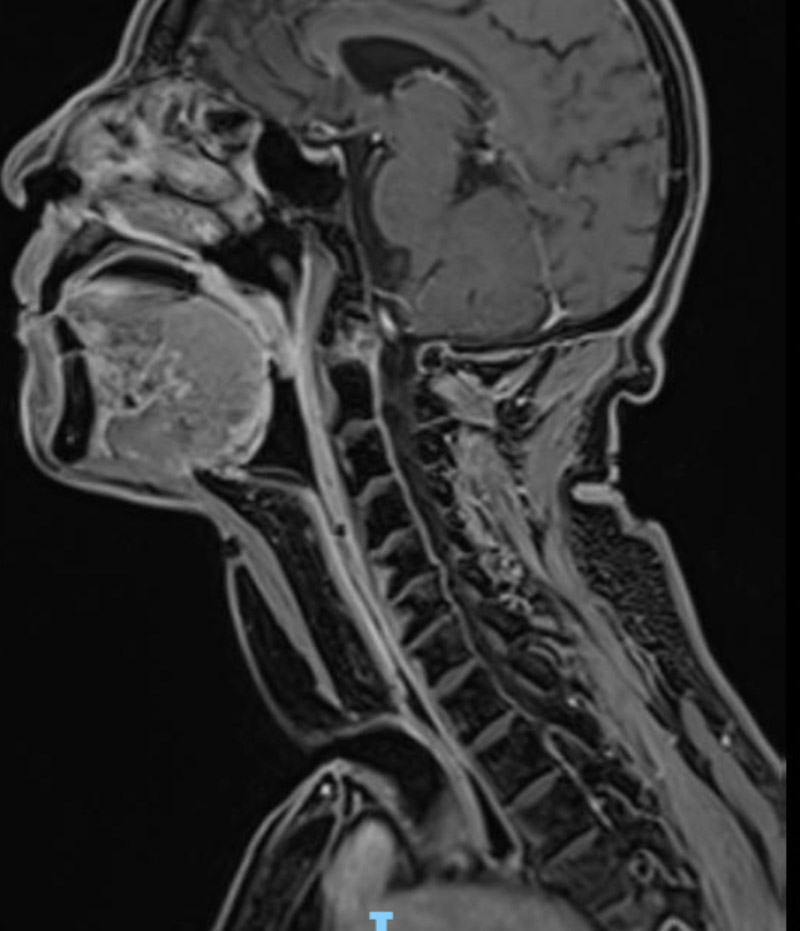

3年前,蔣先生出現(xiàn)聲音嘶啞的癥狀。起初他并沒有引起重視,但隨著時(shí)間的推移,逐漸出現(xiàn)了運(yùn)動(dòng)后呼吸困難、夜間憋醒等癥狀。到當(dāng)?shù)蒯t(yī)院檢查后,提示左側(cè)聲帶及前聯(lián)合占位,再次實(shí)施支撐喉鏡下聲帶腫物切除活檢,病理提示“鱗狀細(xì)胞癌”,遂進(jìn)行了垂直半喉切除術(shù)。

2020年,蔣先生本以為進(jìn)行手術(shù)后身體會(huì)慢慢康復(fù),沒想到在一次復(fù)查中又發(fā)現(xiàn)了喉部腫物,病癥復(fù)發(fā)了……抱著一線希望,他來到了柳州市人民醫(yī)院耳鼻咽喉科。

經(jīng)檢查發(fā)現(xiàn),患者喉癌已侵犯舌根、咽喉后壁、食管上端,病灶范圍廣。因放療無法控制病情,最終頭頸腫瘤MDT團(tuán)隊(duì)決定為其實(shí)施全喉切除+咽后壁、食道上段皮瓣修復(fù)術(shù)。

手術(shù)如期進(jìn)行,耳鼻咽喉科手術(shù)團(tuán)隊(duì)術(shù)中仔細(xì)分離切除腫瘤,取胸部復(fù)合肌皮瓣組織,同時(shí)修復(fù)患者頸部皮膚、下咽和食管上段缺損。這樣一來,既保證了患者正常的飲食功能,又保證了患者的頸部外觀。